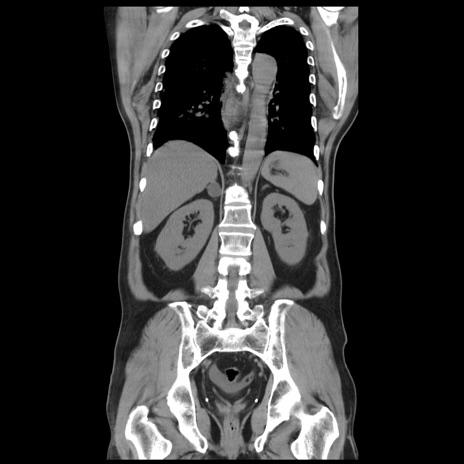

症例20(冠状断像)

【症例】 60歳代男性

【主訴】 腹部膨満、嘔吐

【現病歴】5日前頃より倦怠感を認め食事量減少し4日前の朝嘔吐、食事摂取困難となった。 3日前近医受診し点滴施行され整腸剤などを処方された。 当日他院を受診し、腹部膨満著明、炎症反応の上昇(CRP10.8、WBC11200)あり、紹介受診となる。

【身体所見】 意識JCS1 受け答えがはっきりしないBP 111/57mHg、 P 67bpm、、BT35.2°C、SpO2 97%(RA)、 腹部:膨隆、打診で鼓音あり、全体的に圧痛有り、腸蠕動音(-)、反跳痛ははっきりせず。

【データ】WBC 11400、CRP 14.20